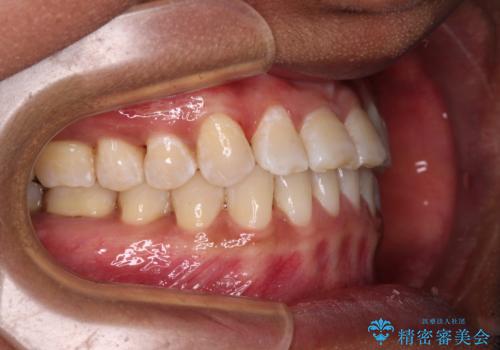

反対咬合の改善 途中で出産をしながらワイヤー矯正

- 前歯の隙間と反対咬合を気にして来院された患者様です。

マウスピース矯正も提案しましたが、しっかりと使用する自信がないとのことで、ワイヤー装置により矯正治療を行うこととしました。

咬合力が強く、反対咬合の改善に時間がかかりましたが、その後はスムーズに進めることができました。

途中、妊娠と出産があり、治療が中断したため、治療期間は延びましたが、出産も矯正治療も無事に終えることができました。